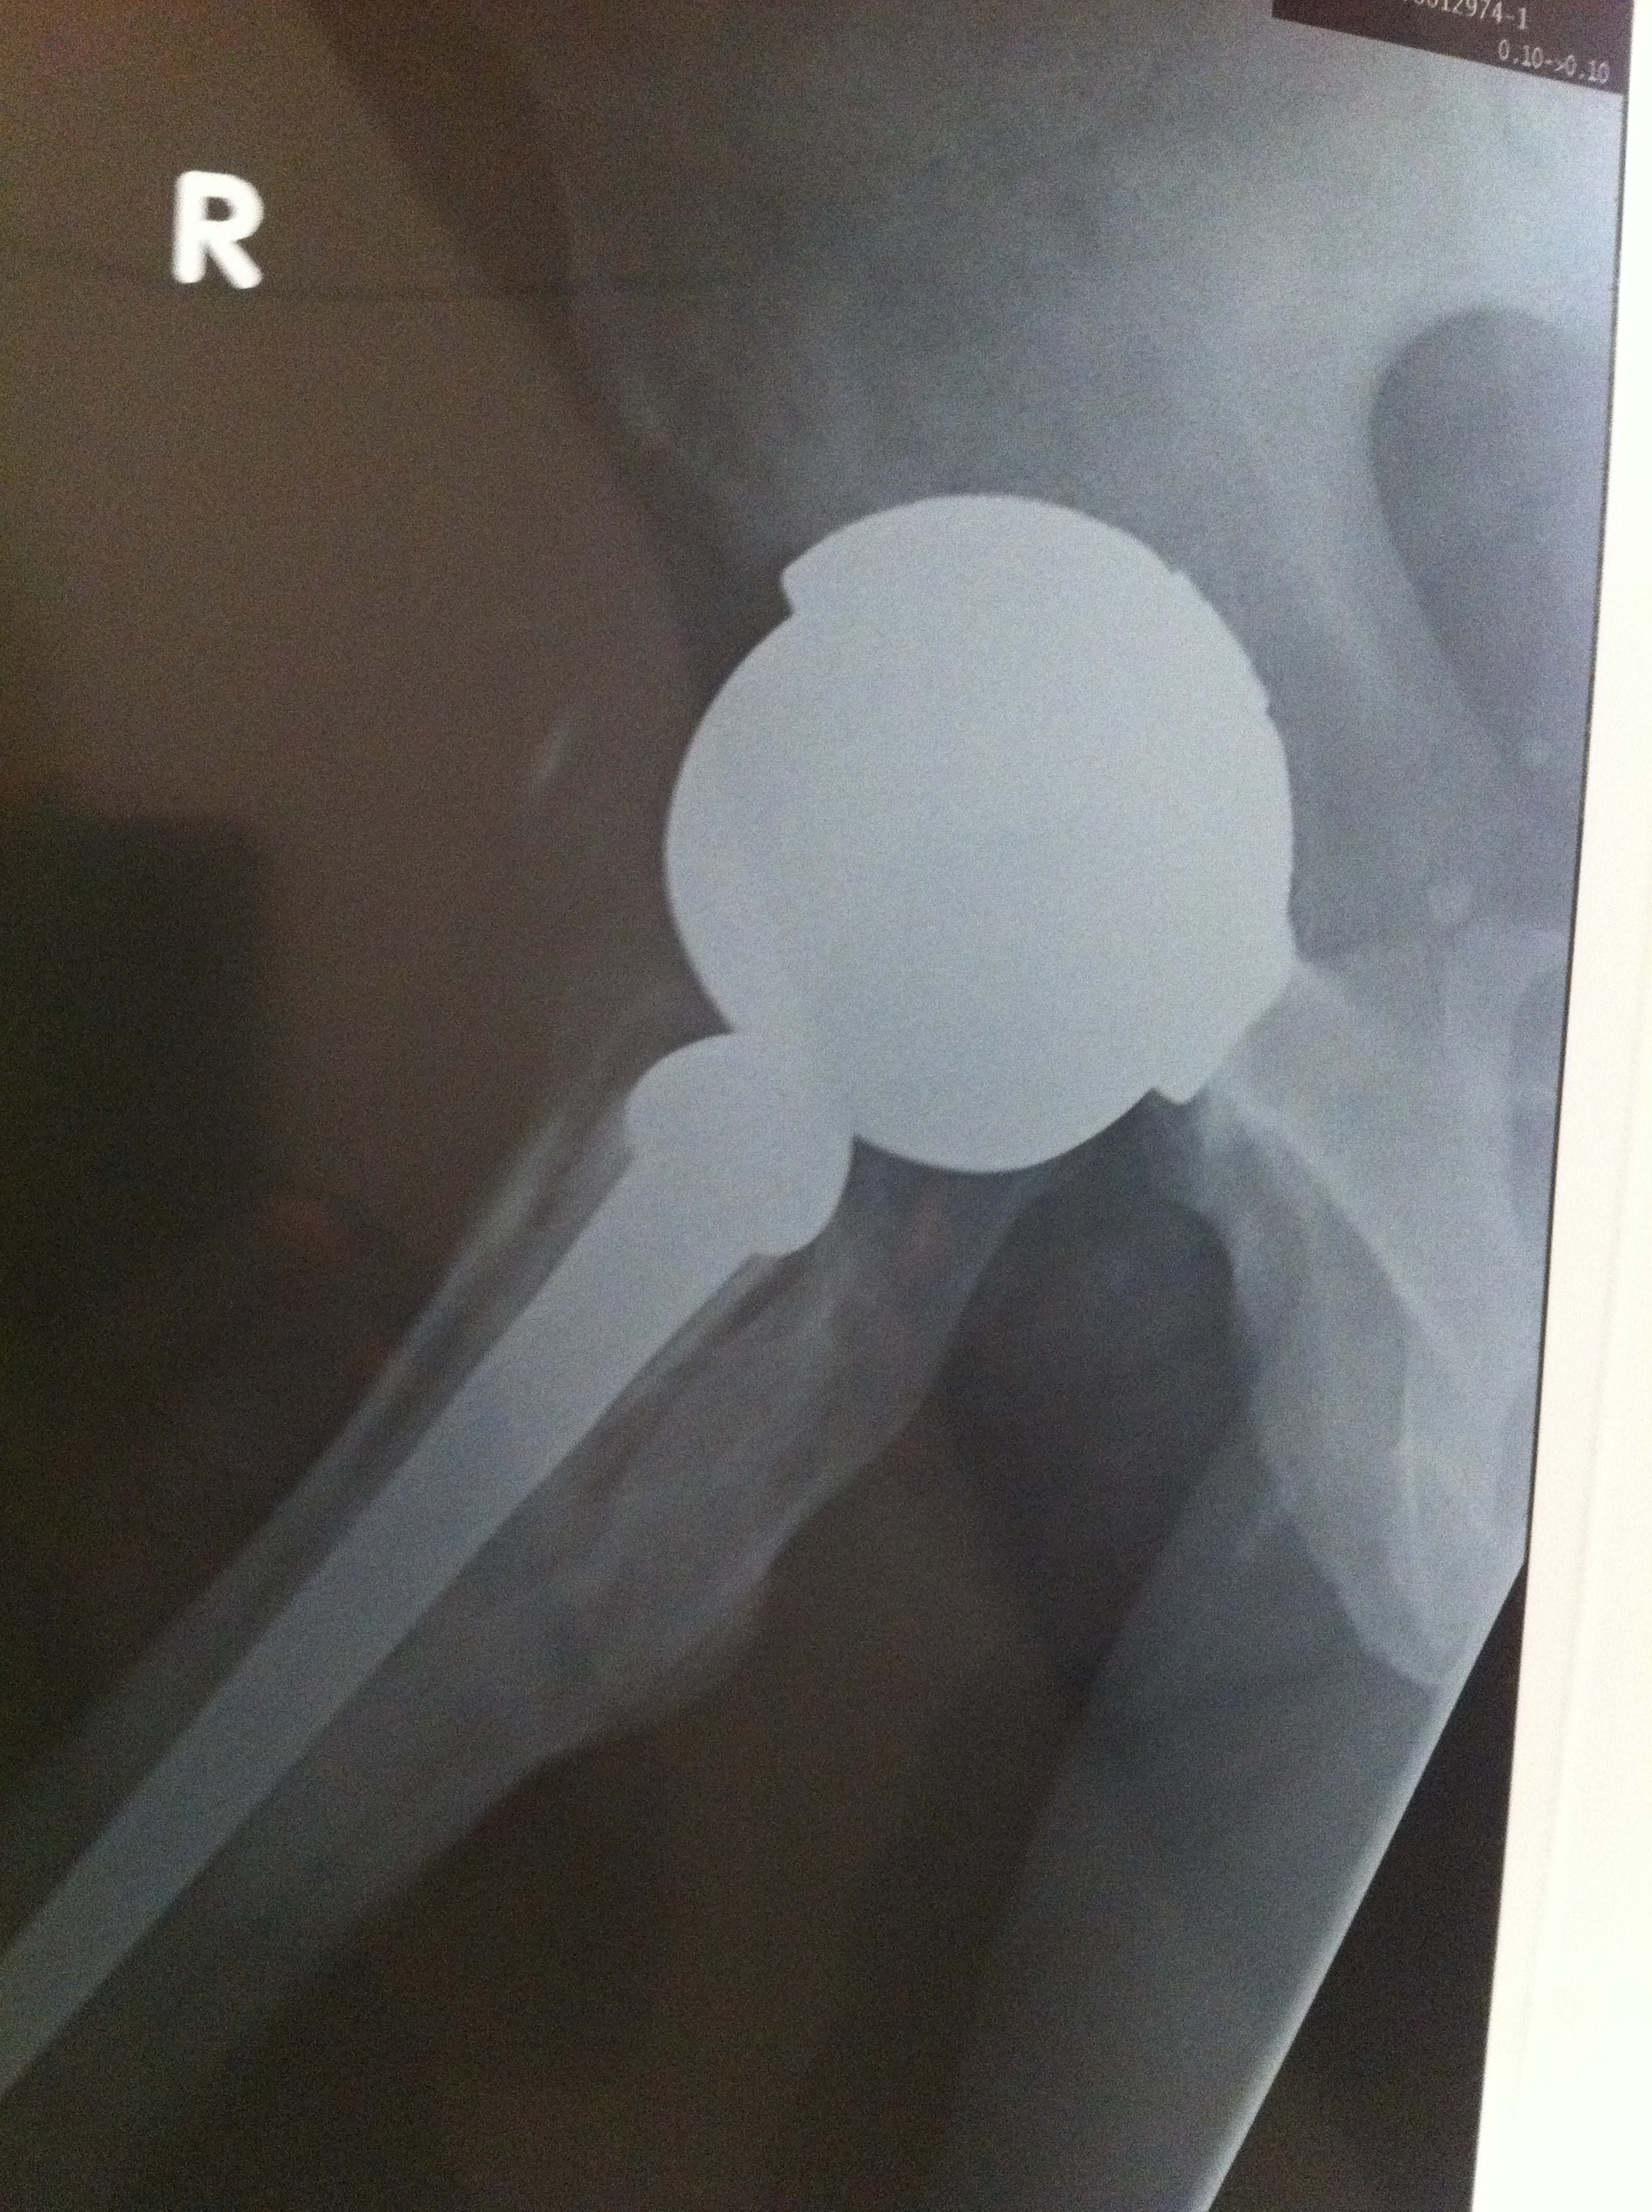

X-rays were taken in the Gold Coast Hospital Outpatients Clinic while I waited – great service – thanks guys!

However, it was the right hip, with the Smith & Nephew Birmingham Spectron total hip replacement which caused the most interest:

- Severe oestolysis around the hip – tissue damage.

- Bone erosion (gone totally) for several centimeters below the collar on the inside leg side.

- Damage to the bone on the outside leg side – mottled and insubstantial-looking.

- Signs of movement of the femoral stem of the hip implant – lines down either side and possible bone damage – the cement contains ceramic and this can then act as a grinding past as the stem moves. This has the potential to release more metal ions.

- These signs of movement may explain the feeling of “popping in and out” that I feel – but without dislocation of the hip prosthesis.

- No cement plug had been used – the surgeon deduced this from the CAT scan I had taken with me.

- Failure to use cement plug meant that the ceramic-polymer cement had gone about twice as far down the centre of the femur as it should have – must have had dramatic consequences for the marrow that was killed/displaced.

- Also failure to use a cement plug had most likely meant that the glue was not forced back up against the femoral implant stem – hence gluing would not have been tight around the femoral stem.

We reviewed my X-rays and confirmed the osteolysis and bone loss. The health of the bone at the top of the femur is a concern and I am going to have a nuclear medicine bone scan tomorrow morning to see what is going on with the blood flow to and around the bone.

The movement of the prosthesis, or lines suggesting movement within the femur where obvious (it seems?).

Had some new X-rays done today – two months since the last ones – seems to me that there is more osteolysis and bone loss – possibly some fragments but I am not a medical doc and I haven’t discussed these with the surgeon yet. Will do on the day of the surgery.

What is interesting is 3 radio-opaque spots showing up in the pelvic area – not sure what those are.

Quality of the photo’s below – OK for an iPhone 4 shot of the X-Rays held up by my son against a white background!